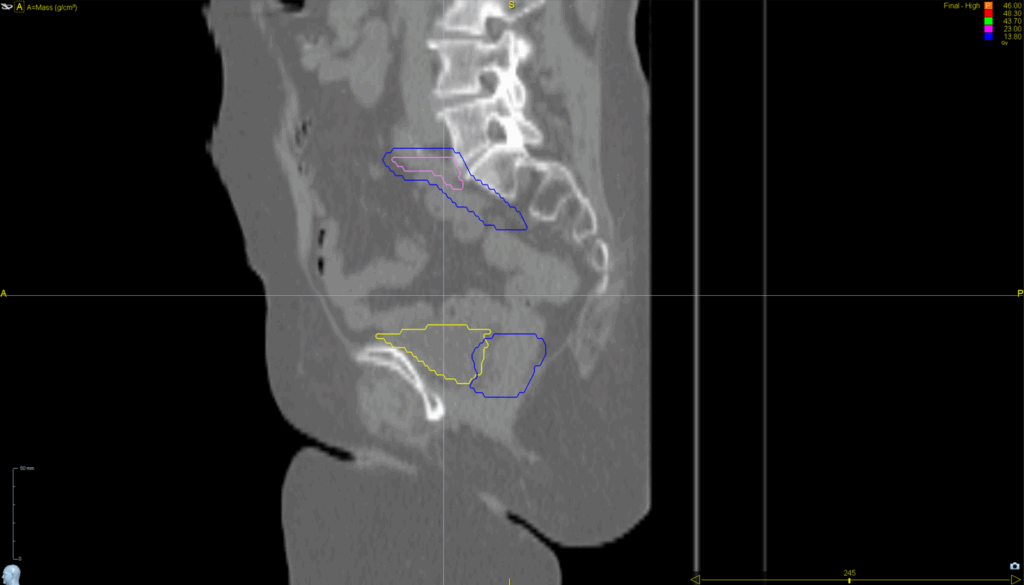

Planning CT Images

PTV(s) Volume, Length

545 cc, 15 cm